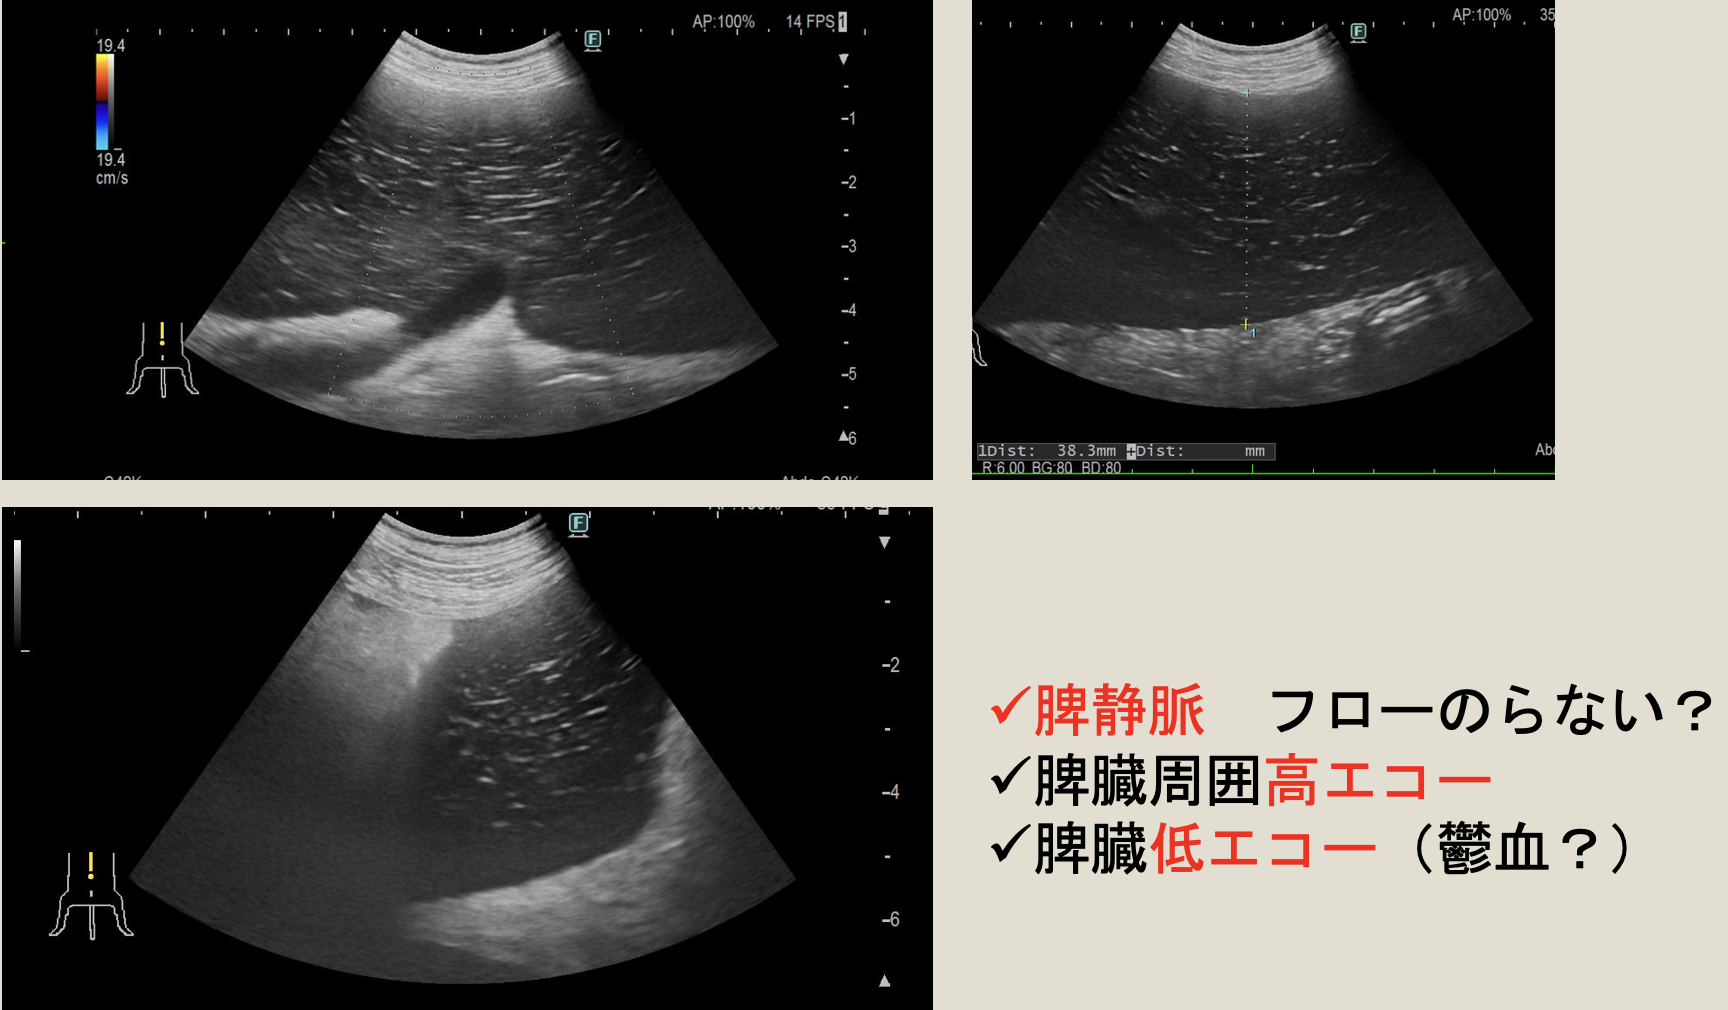

脾臓捻転